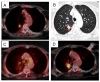

Figure 5 Thumb

Figure 5. Right upper lobe clinical stage IA NSCLC treatment planning PET/CT with a tumor SUVmax of 8.7 (A), planned radiation dose distribution (B: the planning treatment volume receiving 45 Gy in red and the 30 Gy isodose line in blue), and PET/CT at 12, and 24 months post-treatment (C and D) show an initial decrease in SUVmax to 2.3 followed by local recurrence (SUVmax = 8.4).

Click image to view larger.